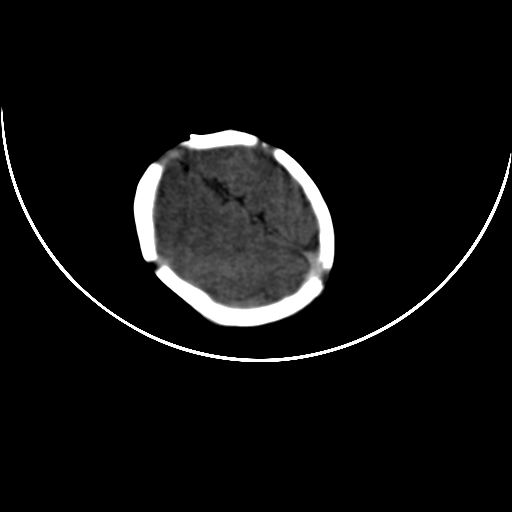

双侧硬膜下血肿并蛛网膜下腔出血。

双侧硬膜下血肿并蛛网膜下腔出血

双侧硬膜下血肿并蛛网膜下腔出血,考虑维生素k缺乏引起.

较大范围出血,应考虑维生素k缺乏引起,结合临床吧。